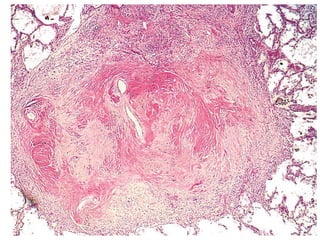

Morphology

• Reid index ratio i.e the thickness of the

mucus gland layer to the bronchial wall

Ctd…

• Reid index (normally 0.4) is increased

• Bronchial epithelium may exhibit squamous

metaplasia & dysplasia

• Marked narrowing of bronchioles

• In severe cases, bronchiolitis obliterans